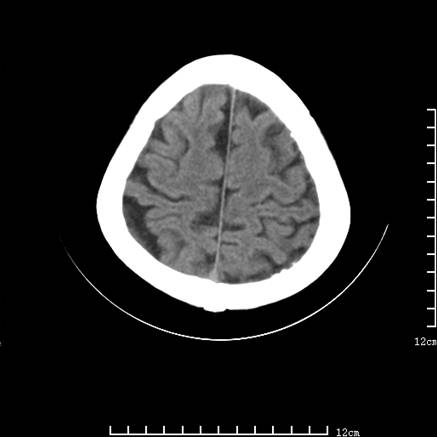

标题: V0514:女,72岁,偶有头晕,自诉记忆力减退,来诊。 [打印本页]

标题: V0514:女,72岁,偶有头晕,自诉记忆力减退,来诊。

2、脑萎缩ct表现。

垂体腺瘤可能性大!另:轻度脑萎缩!